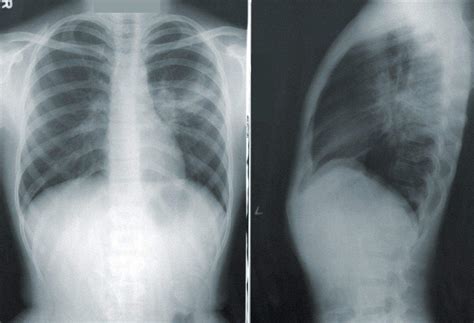

• Chest X-ray: This can show areas of inflammation or fluid in the lungs.